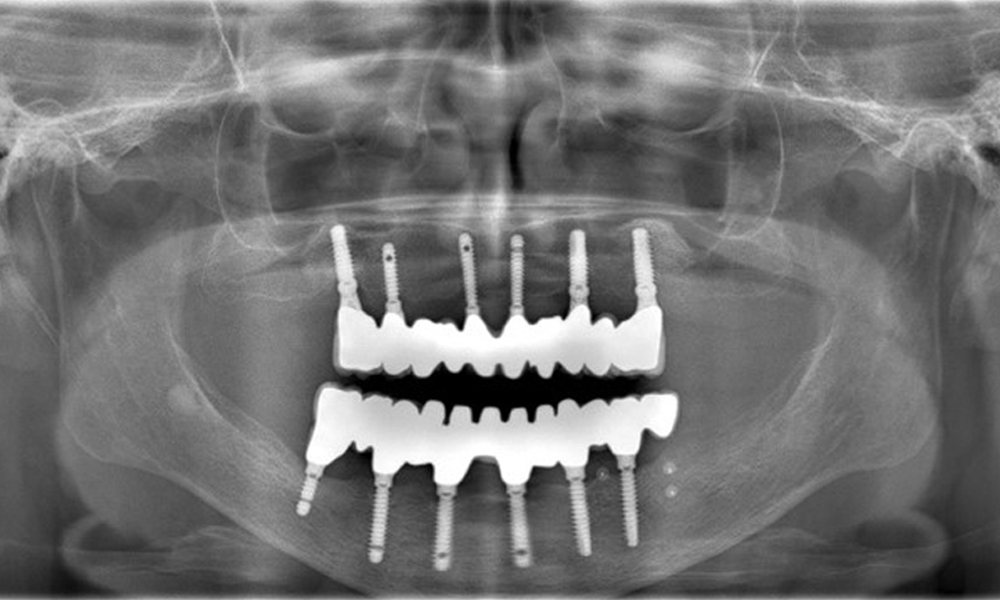

A 74-year-old patient presents for a consultation. The anamnesis shows that the patient has well-controlled hypertension and is taking Lixiana. Additionally, the patient had a kidney carcinoma in 2020. The patient’s lifestyle is unremarkable. She has no natural teeth left and has six implants in both the upper and lower jaws, which are fitted with crowns or bridges. Current findings show no peri-implant mucositis or peri-implantitis; however, there are occasional minor bleeding at the implant sites.

Provisions: Implants in regions 011, 013, 015, 021, 023, 025, 031, 033, 035, 042, 044, 046

The radiographic images reveal bone resorption.

Figure 2: The radiographic images reveal bone resorption.